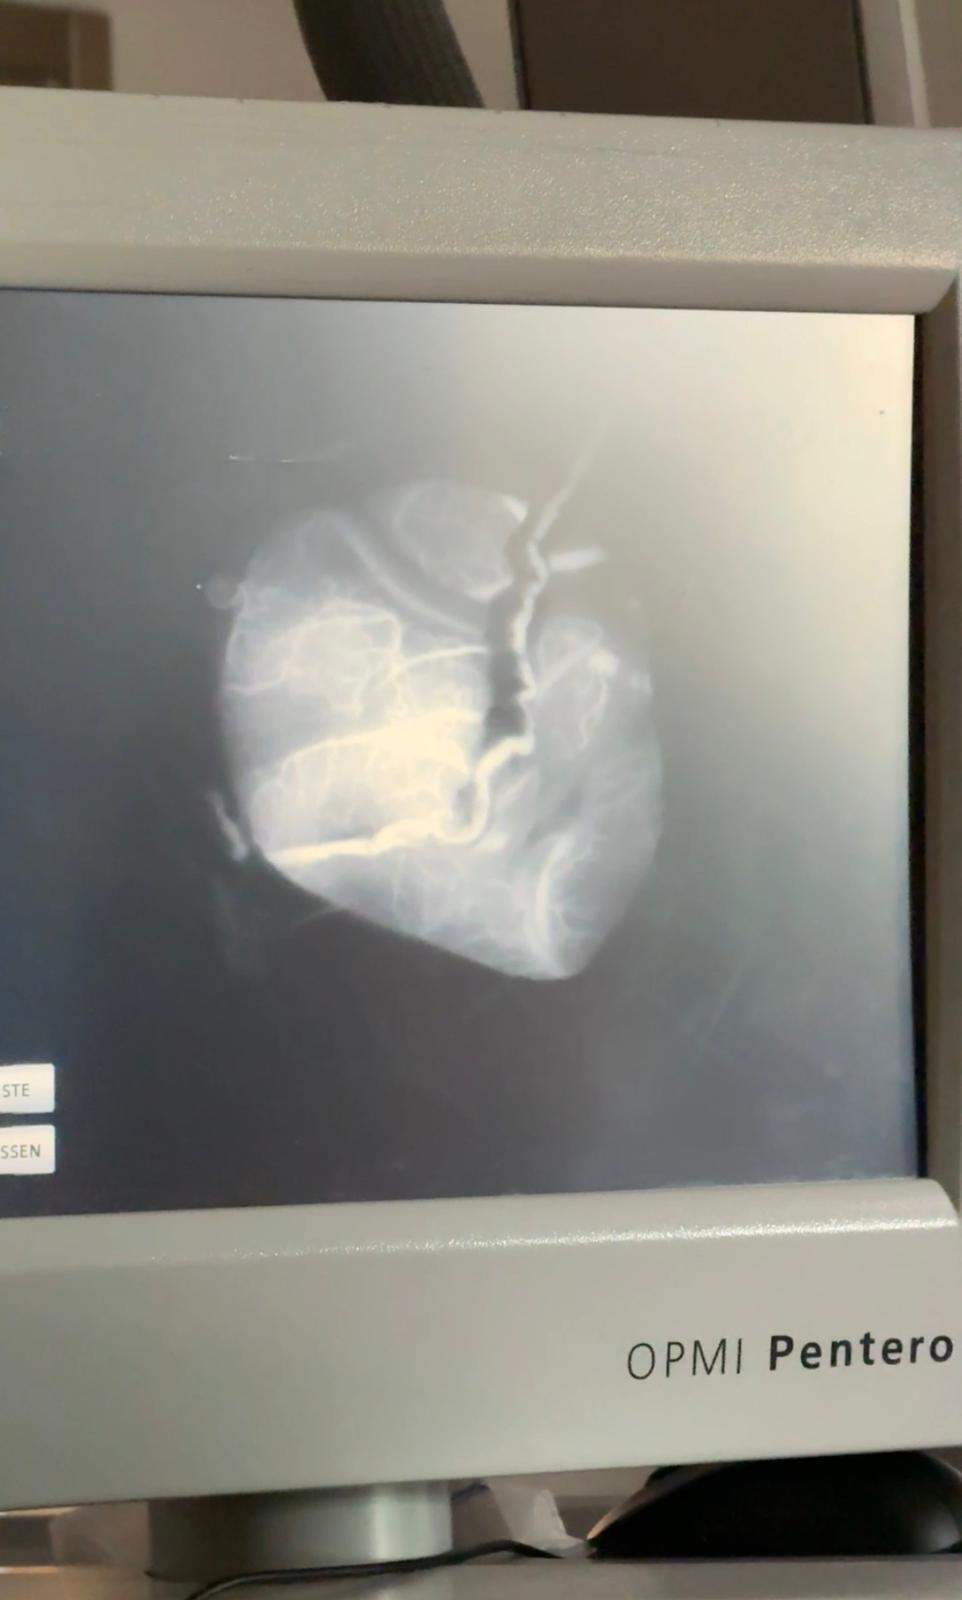

Wir, zwei Schüler der Klasse 5BT2, haben im Zuge unseres Erasmus+-Betriebspraktikums für zwei Wochen an der Charité-Berlin in der Klinik für Neurochirurgie mit Schwerpunkt pädiatrische Neurochirurgie am Campus Berlin Mitte gearbeitet.

Im Rahmen von Visiten, ambulanten Sprechstunden und Behandlungen wurde es uns ermöglicht, einen Überblick über den gesamten Arbeitsalltag der Ärzte auf der neurochirurgischen Station der Charité zu erhalten und unsre fachlichen Kenntnisse zu vertiefen.

Besonders spannend war natürlich der Alltag im Operationssaal. Unter der Leitung des renommierten Prof. Dr. Peter Vajkoczy waren wir bei zahlreichen neurochirurgischen Operationen dabei. Hervorzuheben sind dabei die komplexen und Innovativen Behandlungs- und Operationsmethoden, die an der Charité entwickelt und angewandt werden und für welche sie auch international bekannt ist.